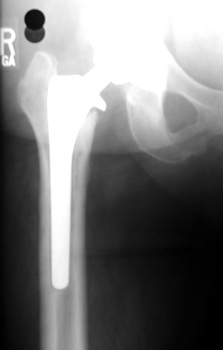

LOOSENING

No prior studies available. Abnormally widened interfaces surrounding entire cement mantle of femoral component, consistent with loosening.